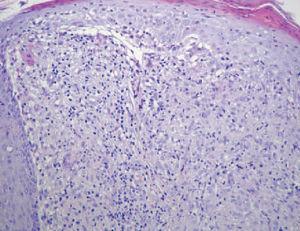

El estudio histológico reveló un intenso infiltrado inflamatorio en la dermis papilar y reticular superficial, constituido por linfocitos y abundantes histiocitos epitelioides, que formaban granulomas tuberculoides no caseificantes parafoliculares. Éstos alcanzaban incluso a la capa basal epidérmica, causando su degeneración vacuolar (fig. 2). Otras alteraciones epidérmicas consistían en la presencia de acantosis, paraqueratosis focal y espongiosis. El resto de pruebas complementarias realizadas incluyendo analíticas básicas, enzima conversora de angiotensina, cinc sérico, prueba de Mantoux, radiografía de tórax, y cultivo de una muestra de las lesiones, resultaron normales o negativas.

Fig. 2. Granulomas tuberculoides en dermis papilar que alcanzan la capa basal epidérmica. (Hematoxilina-eosina, ×250.)

En general, el estudio histopatológico en la dermatitis perioral coincide con el de la rosácea, con mínimos cambios epidérmicos, infiltrados linfohistiocitarios perivasculares o perifoliculares con ectasia vascular. Cuando aparecen granulomas, estos se describen como estructuras tuberculoides dérmicas9 , para o perifoliculares, sin necrosis central, idénticos a aquellos de la variante granulomatosa de la rosácea4 .